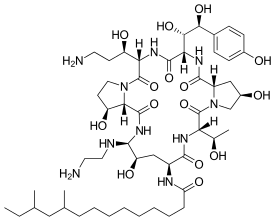

Chemistry

The present-day clinically used echinocandins are semisynthetic pneumocandins, which are chemically lipopeptide in nature, consisting of large cyclic hexapeptoids. Caspofungin, micafungin, and anidulafungin are similar cyclic hexapeptide antibiotics linked to long modified N-linked acyl fatty acid chains. The chains serve as anchors on the fungal cell membrane to facilitate antifungal activity.[9] Due to their limited oral bioavailability, echinocandins are administered through intravenous infusion.[10]